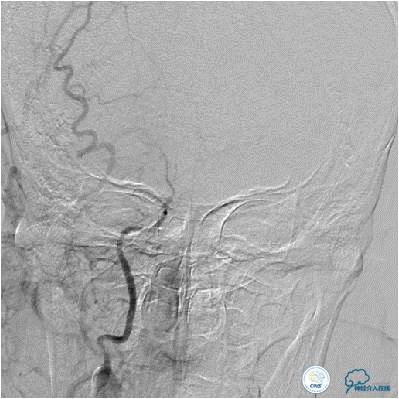

患者入院后,完善颅内CTA(图1)及血管造影(图2~3)检查,发现右侧颈内动脉颅内段闭塞,右侧大脑前动脉依靠左侧颈内动脉系统通过前交通动脉供血,右侧大脑中动脉供血区则依赖于右侧大脑前动脉(ACA)软脑膜代偿供血,左侧大脑中动脉闭塞,依靠一少见血管代偿供血,该血管起自左侧大脑前动脉A2段起始部,代偿供应左侧大脑中动脉供血区。由于该患者灌注CT(图4)未见明显低灌注区,遂给予患者抗血小板、降脂及控制危险因素治疗出院。出院后电话随访未再出现过上述症状。

图1:三维造影提示左侧大脑中动脉闭塞,左侧大脑中动脉由一异常血管供血,考虑为Heubner返动脉。